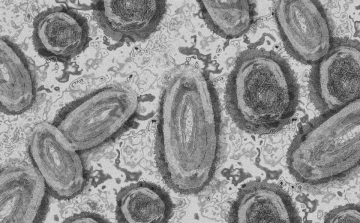

Tovább nőtt a majomhimlő-fertőzöttek száma Magyarországon

Újabb két embernél igazolt majomhimlő-fertőzést a Nemzeti Népegészségügyi Központ (NNK) a 33. héten - augusztus 15-től 21-ig -, ezzel 64-re nőtt a magyarországi esetek száma.

Egy 3 év alatti gyermek fertőződött meg majomhimlővel Belgiumban

Belgiumban egy 3 év alatti gyermek fertőződött meg majomhimlővel - számolt be róla szerdán a Sudinfo hírportál.

Megfertőződött a majomhimlővel egy gyerek Németországban

Megfertőződött majomhimlővel egy négyéves kislány Németországban - jelentették kedden német hírportálok az országos közegészségügyi intézet (RKI) adatai alapján.